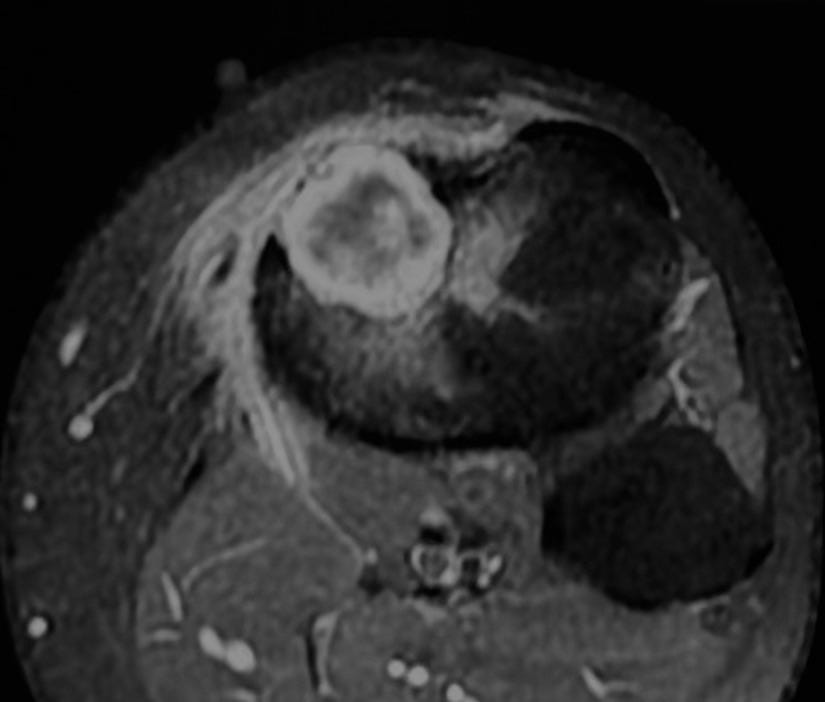

MRI shows marrow edema - this is now a “benign aggressive” lesion.

The lesion is partly T2 dark and shows a lamellated pattern of enhancement and is eccentric juxtamedullary.